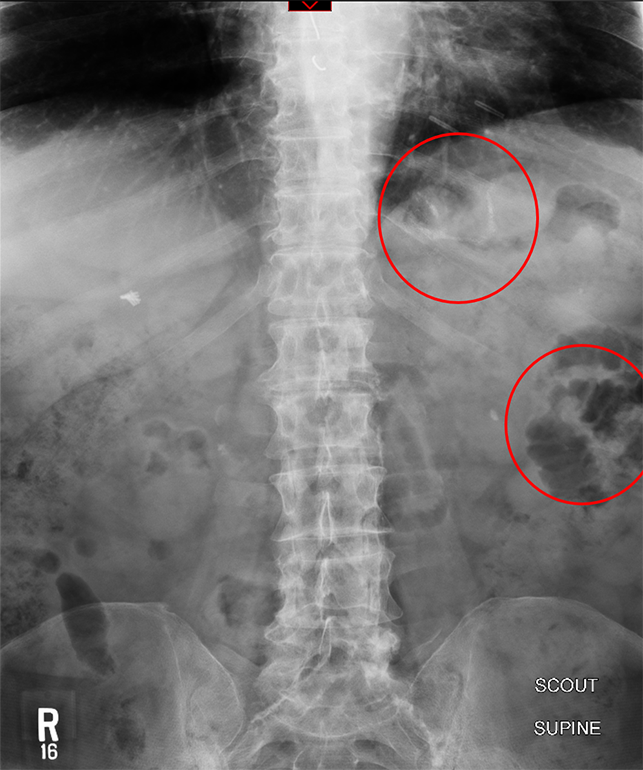

- The technologist will obtain a scout image. Assess the image for any possible contraindications such as pneumoperitoneum, evidence of ileus or obstruction, or residual contrast material

(key image 1).